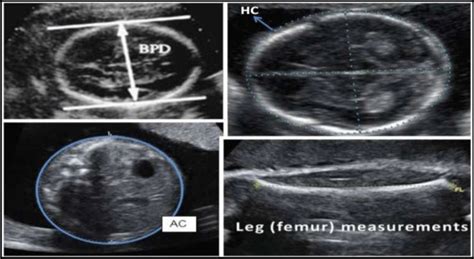

Biparietal Diameter (BPD)

First up, we have the Biparietal Diameter , or BPD . This one is all about your baby’s head. Specifically, it measures the widest part of the fetal skull, from one parietal bone to the other, usually at a level that includes the thalami and the cavum septum pellucidum. Why is this important? Well, the BPD gives a good indication of the baby’s head circumference and growth. It’s one of the primary measurements used to estimate gestational age, especially in the second trimester. A consistent BPD measurement helps ensure the baby’s head is growing proportionally. It’s also a crucial marker when doctors are assessing for potential issues with fetal brain development or head shape abnormalities. When they’re looking at the BPD, they’re essentially measuring the width of the skull, which helps them gauge the overall size of the head. This measurement, along with others, contributes to the estimation of the baby’s age and expected delivery date. It’s fascinating how they can get such precise measurements from the outside, right? The BPD is a foundational measurement in assessing fetal head growth.

Head Circumference (HC)

Next, we have the Head Circumference , or HC . This measurement essentially circles around the baby’s head, following the same plane as the BPD. Think of it as the BPD’s broader cousin, giving a more comprehensive idea of the baby’s head size. The HC is calculated using the BPD and sometimes the occipitofrontal diameter (OFD) and is another vital parameter for assessing fetal growth and gestational age. A well-proportioned HC relative to other measurements suggests normal head development. If the HC seems significantly larger or smaller than expected based on gestational age, it can prompt further investigation into potential conditions like microcephaly (abnormally small head) or macrocephaly (abnormally large head), or even issues related to fetal brain development. It’s all about ensuring that the head is growing at a rate that aligns with the rest of the baby’s body. The HC provides a circumferential view of fetal head growth.

Abdominal Circumference (AC)

Now, let’s move down to the Abdominal Circumference , or AC . This measurement is exactly what it sounds like: it measures the circumference of the baby’s abdomen at a specific level, usually encompassing the stomach, the umbilical vein, and the left portal vein. Why focus on the tummy? Because the baby’s abdominal growth is heavily influenced by factors like the liver and intestines, which are crucial for fetal nutrition and growth. The AC is a really important indicator of fetal weight and growth, especially in the later stages of pregnancy. It helps doctors assess if the baby is receiving adequate nutrition and growing appropriately. Discrepancies in AC compared to other measurements might suggest issues with placental function, fetal nutrition, or certain fetal conditions affecting the liver or other abdominal organs. The AC is a key indicator of fetal weight and nutritional status. It’s where the magic of nutrient absorption and processing happens, so its growth is super telling.

Femur Length (FL)

Finally, we have the Femur Length , or FL . This one is pretty straightforward: it measures the length of the baby’s femur, which is the thigh bone. It’s the longest bone in the body and a very reliable indicator of skeletal growth. The FL measurement is particularly useful for estimating gestational age and assessing skeletal development. Since long bones tend to grow at a predictable rate, the FL is less affected by factors like amniotic fluid levels or maternal abdominal fat compared to circumference measurements. A normal FL measurement, when correlated with BPD and AC, helps confirm the overall growth pattern. Significant deviations in FL might raise concerns about skeletal dysplasia (disorders affecting bone and cartilage) or other growth abnormalities. The FL is a crucial measure of fetal long bone and skeletal growth. It gives us a peek into how the baby’s